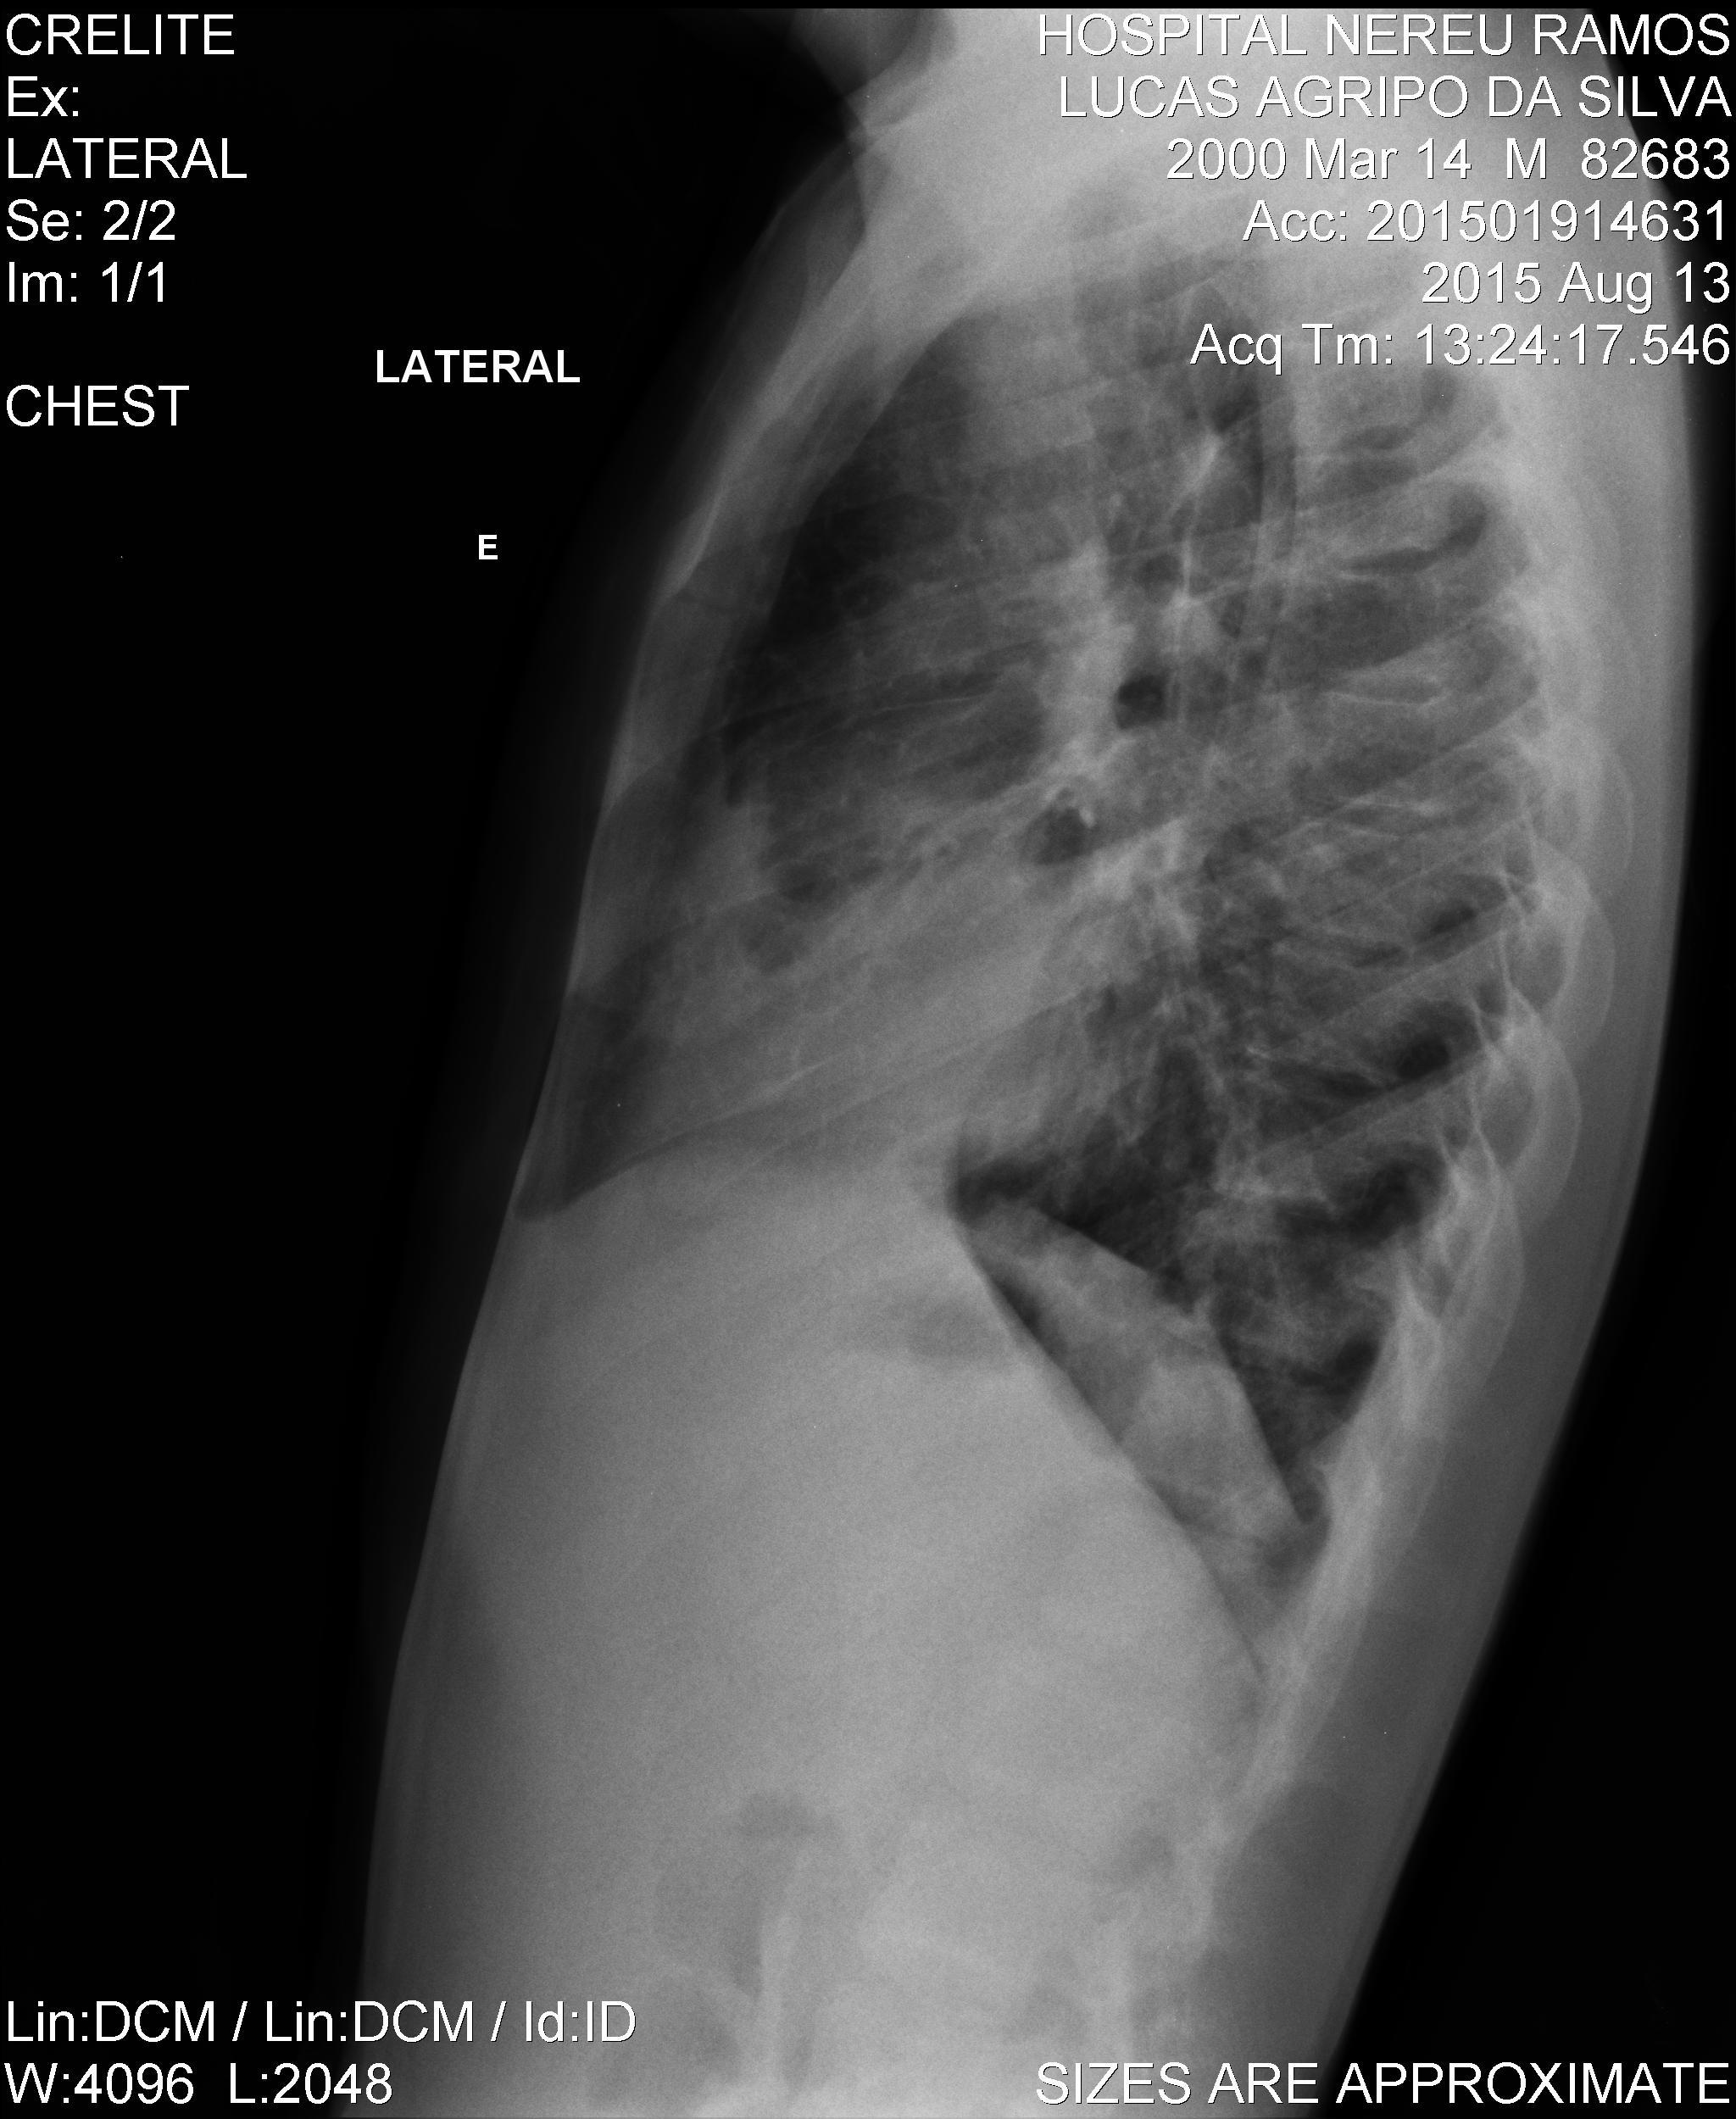

Caso Número 4/2018: “Uma sessão interativa de casos em radiologia torácica – Parte 1”

Caso relatado na Reunião de Discussão de Casos Clínicos do Hospital Universitário Prof. Polydoro Ernani de São Thiago, iniciada pelos Profs. Jorge Dias de Matos, Marisa Helena César Coral e Rosemeri Maurici da Silva, em julho de 2017. No dia 14 de junho de 2018, no auditório do HUPEST, realizou-se a apresentação e discussão do caso cujo registro é apresentado a seguir. Trata-se da discussão de onze casos em radiologia torácia, de forma interativa com a plateia, e assim ocorre também neste artigo.